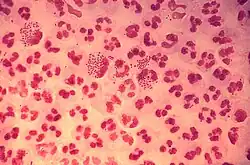

Die Gonorrhoe (auch Gonorrhö und Gonorrhöe, von altgriechisch γονόῤῥοια gonórrhoia, wörtlich „Samenfluss“) ist eine der häufigsten sexuell übertragbaren Erkrankungen. Diese bakterielle Infektionskrankheit befällt die Schleimhäute von Harn- und Geschlechtsorganen. Ausgelöst wird sie durch 1879 erstmals mikroskopisch nachgewiesene Gonokokken (Neisseria gonorrhoeae), aerobe (sauerstoffabhängige), gramnegative, bewegliche Bakterien, die als sogenannte Diplokokken paarweise auftreten.

Die Bakterien heften sich an die Schleimhautzellen der Harnröhre beziehungsweise des Gebärmutterhalses an. Dazu dienen spezielle Pili, aus Proteinen bestehende fadenförmige Fortsätze an der Bakterienwand. Dabei spielt das Adhäsin Pilin eine große Rolle.

Manche Stämme regen die Schleimhautzellen dazu an, sie aufzunehmen (Phagozytose) und auf der anderen Lumen-abgewandten Seite wieder auszuwerfen. Dieser Prozess wird als Transzytose bezeichnet. Die Phagozytose wird durch Opa-Proteine (für opacity „Trübung“, da sie die Kolonien trübe erscheinen lassen) induziert.

Gonokokken werden von Granulozyten (Zellen des Immunsystems) phagozytiert und können daher vom Körper meist auch abgetötet werden. Nur ein Teil überlebt in den Zellen. Die Gewebeschädigung erfolgt durch Auslösen einer eitrigen Entzündung mit Komplementaktivierung und dadurch bedingter Zerstörung der befallenen Deckzellen. Dafür scheint vor allem das Lipopolysaccharid der Bakterienzellwand eine große Rolle zu spielen.

Aus dem Harnröhrensekret oder dem Sekret des Gebärmutterhalses kann ein Abstrich entnommen werden und der Erreger mikroskopisch mit Hilfe der Gram-Färbung oder in der Kultur nachgewiesen werden. Während dieser Nachweis bei symptomatischen Männern sehr genau ist, ist er bei Zervizitis nur in etwa 50 % der Fälle positiv. Ein anderes Verfahren ist der Nachweis von für Neisseria gonorrhoeae spezifischen Nukleinsäuren. Die Sensitivität dieses Tests ist vergleichbar mit derjenigen herkömmlicher Kulturen, er ist aber preiswerter.